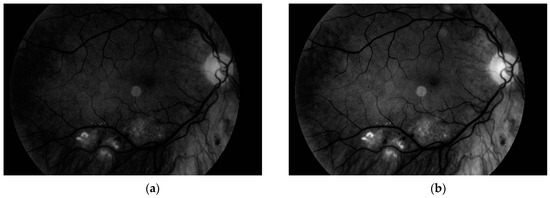

where S k is the new value for k-th level, S k is the original value for k-th level, k m i n and k m a x are minimum and maximum level, respectively, in the original histogram, whilst Z k is number of new possible ranges. In this case, Z k = 256 because we use all values from 0 to 255. The result obtained with this operation is presented in Figure 6.

Figure 6. (a) Grayscale image and (b) its form after histogram stretching.